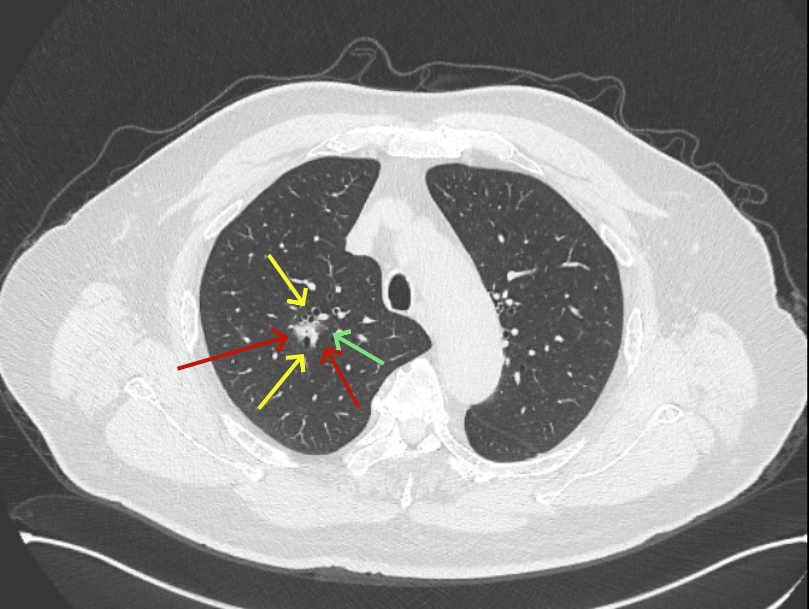

病灶B似乎灶内有少许密度略偏高,但瘤肺边界欠清晰,总体说不上太显著的进展。

当时结友自己还觉得有点实性成分,血管感觉也有增粗。而我觉得整体密度仍是磨玻璃,轻微的变化仍不足以影响临床决策的程度。

但病灶B却显然进展!变成以实性成分为主的了!